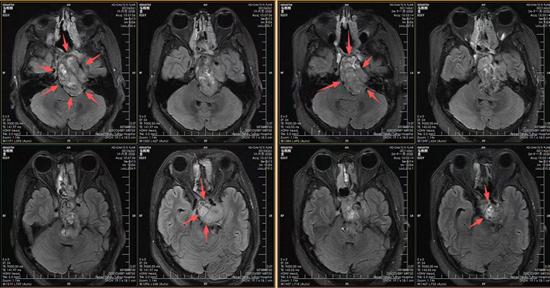

质子治疗前后影响对比图

夏晓年半年后的随访也给所有人吃下了一颗定心丸。影像显示病灶明显缩小,压迫明显缓解,相关症状逐渐改善。那个被肿瘤长期追赶、压得无法喘息的年轻人,终于第一次感觉到自己不是在“被赶着跑”,而是可以真正向前走了。